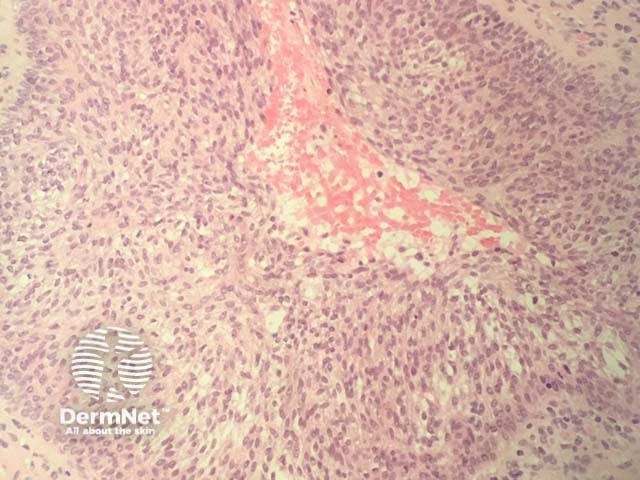

Tumour stage: when tumours start to form clinically, histopathology shows a much denser dermal infiltrate (figure 4). There may be no exocytosis of lymphocytes in this stage. Transformation to large cells may occur (figure 5).

Figure 5